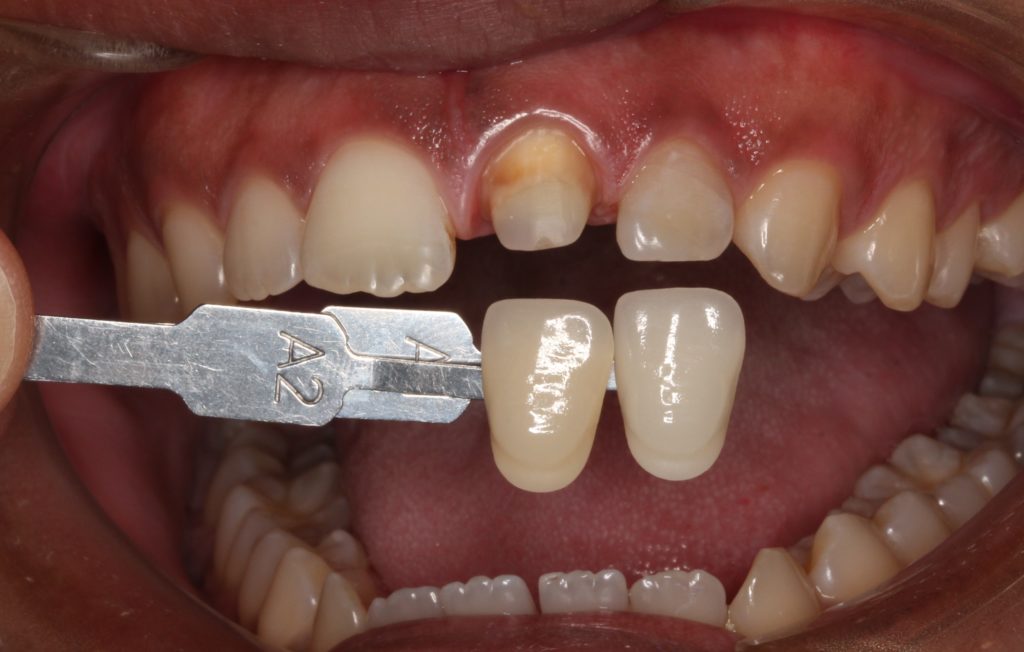

歯の型取りと、色合わせです。

歯の色見本と照らし合わせて記録します。周囲の歯の色に合わせてクランを製作します。